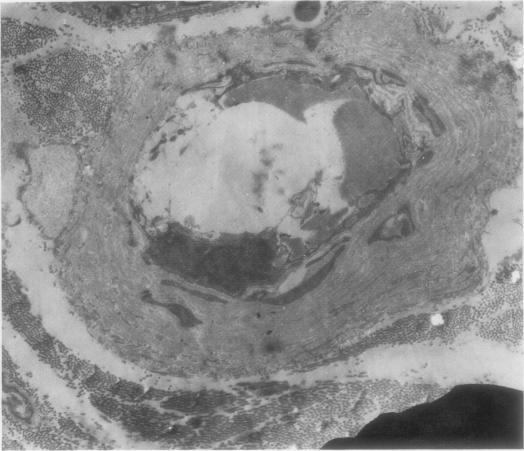

the results of an electron microscopical study of sural nerve biopsies from 11 patients with diabetic neuropathy are presented. Thrombi were seen in six cases in at least one intraneural vessel; nine cases showed hyperplasia of endothelial cells, and in seven out of these nine the hyperplasia was sufficient to occlude completely the lumen of small vessels; six cases showed degenerate pericytes and endothelial cells, and in some cases endothelial cells had been shed from the vessel wall, exposing the blood within the vessel to the underlying basement membrane; in five cases large lipid droplets were seen within endothelial cells. Abnormalities of the vessel wall would result in decreased fibrinolytic activity and a reduction of the antiplatelet aggregating proprties of the vessel. Desquamation of endothelial cells from the vessel wall, with exposure of platelets to underlying collagen, may act as a trigger for thrombus formation, particularly as the blood of diabetic patients is often in a hypercoagulable state. The significance of hyperplasia of endothelial cells is at present unknown but, once established, this too would result in profound alterations of loal blood flow and ischaemia of nerve. Damage to endothelial cells may also allow seepage of haematological constituents into the vessel wall, resulting in its progressive thickening.

本文展示了对11例糖尿病性神经病变患者腓肠神经活检的电子显微镜研究结果。在至少一条神经内血管中,6例可见血栓;9例显示内皮细胞增生,其中7例增生足以完全阻塞小血管腔;6例显示周细胞和内皮细胞变性,在某些情况下,内皮细胞从血管壁脱落,使血管内的血液暴露于下方的基底膜;5例在内皮细胞内可见大脂滴。血管壁异常会导致纤溶活性降低以及血管抗血小板聚集特性降低。内皮细胞从血管壁脱落,使血小板暴露于下方的胶原蛋白,可能触发血栓形成,特别是因为糖尿病患者的血液通常处于高凝状态。目前尚不清楚内皮细胞增生的意义,但一旦形成,这也会导致局部血流的深刻改变和神经缺血。内皮细胞损伤还可能使血液成分渗入血管壁,导致血管壁逐渐增厚。